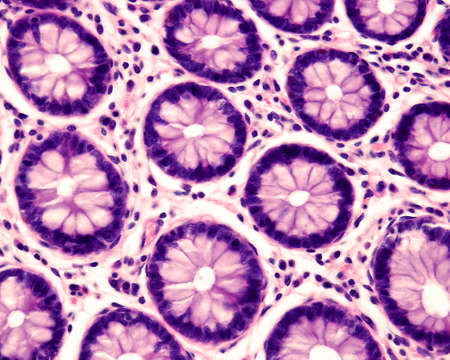

Cross section of intestinal glands (crypts of Lieberkühn) showing mucous goblet cells. Human colon.